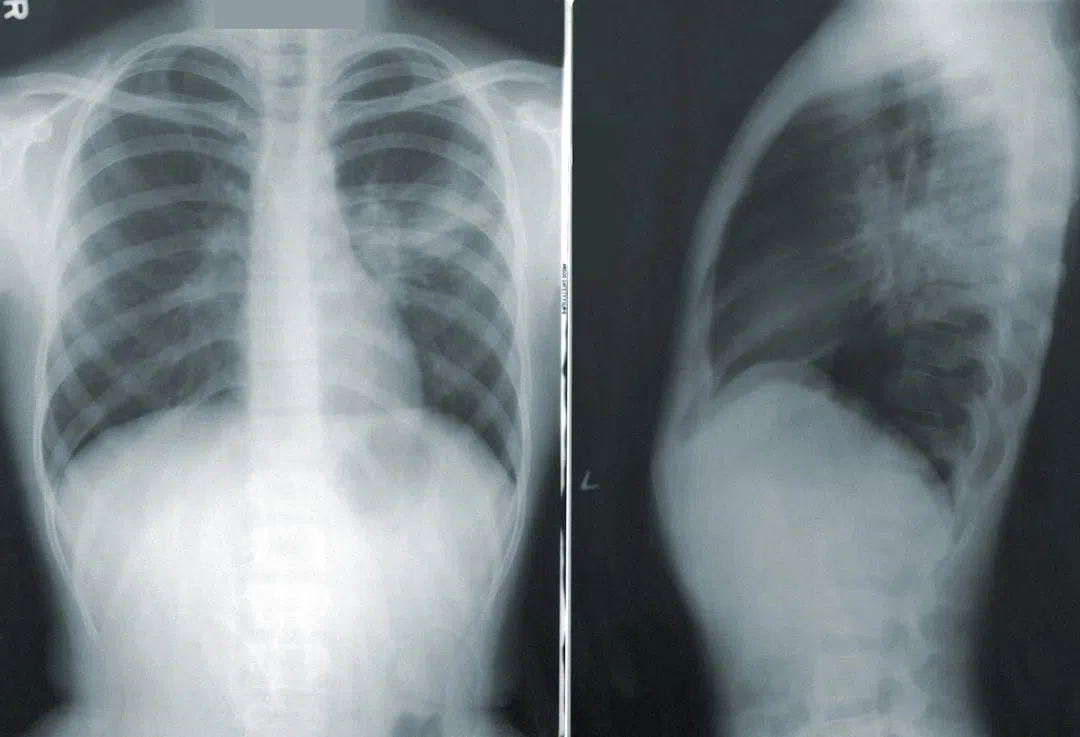

폐에 문제가 있음을 암시하는 기침과 통증은 내 체력과 면역력 저하에 영향을 미쳤습니다. 의사와 상담 후 추가 검사를 받게 되었고, 그 과정에서 폐 기능 검사와 흉부 X-ray, CT 스캔 등을 통해 폐 내부 구조를 꼼꼼히 확인할 수 있었습니다. 검사 결과 폐의 염증이나 감염 가능성은 배제되었지만, 반복되는 기침은 여전히 내 몸에 큰 부담으로 남아 있었습니다.